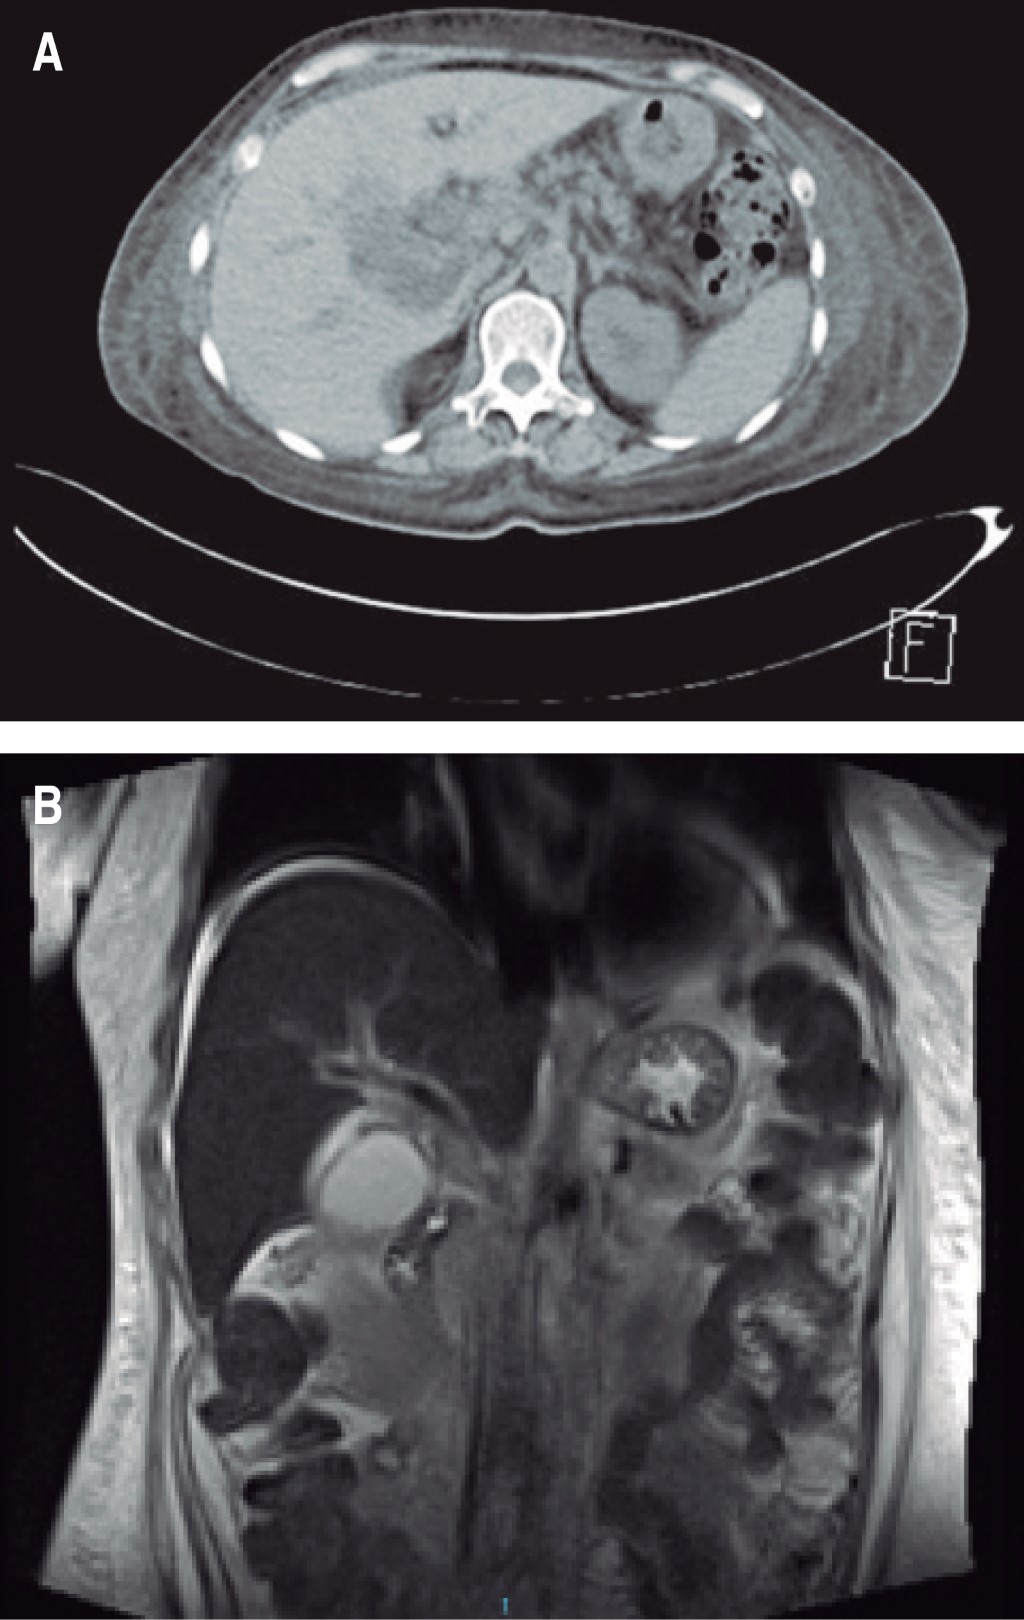

Se identificó y clasificó el grado de daño renal de acuerdo a los valores de creatinina en los primeros laboratorios, los de seguimiento y a su egreso, el resultado fue que 80% de los individuos se clasificaron en estadio III, según AKIN (Tabla 2). El estudio de imagen para iniciar el abordaje es el ultrasonido abdominal y a fin de valorar la evolución del paciente se solicitó TAC abdominopélvica (Figura 1).

El tratamiento médico se focalizó en dos puntos: el apoyo mediante fármacos vasopresores y la terapia antibiótica. El 60% requirió aminas y respecto al empleo de medicamentos antimicrobianos el principal antibiótico empírico empleado fue la ceftriaxona (35.7%) a modo de monoterapia iniciada como esquema prehospitalario. En la etapa de hospitalización, se cambió a un fármaco de mayor dispersión siguiendo las recomendaciones de guías internacionales; en esta serie el antibiótico iniciado fue imipenem (21.4%) (Figura 2). En días, la duración media de terapia antimicrobiana fue de 23.4, sin embargo la media del lapso de estancia intrahospitalaria fue de 18.2, lo cual representa un periodo largo de tiempo. Finalmente, en la resolución quirúrgica, el 60% precisó drenaje percutáneo y sólo un 40% fue candidato a laparoscopia.